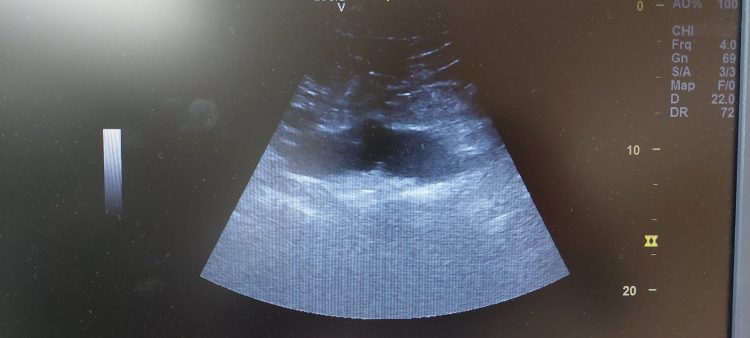

Tokom tri mjeseca trajanja programa, ukupno 30 doktora, specijalista porodične i urgentne medicine, pregledalo je 1.207 pacijenata, a zahvaljujući preventivnim pregledima otkriveno je 12 aneurizmi abdominalne aorte. Skrining je bio namijenjen osobama starijim od 55 godina, oba pola, koje ranije nisu imale dijagnostikovanu aneurizmu abdominalne aorte.

Aneurizma abdominalne aorte predstavlja ozbiljno i često asimptomatsko oboljenje koje se razvija tiho, dok njena ruptura nosi izuzetno visoku smrtnost. Upravo zbog toga rano otkrivanje ima presudnu ulogu u spašavanju života i sprječavanju teških, često fatalnih komplikacija.